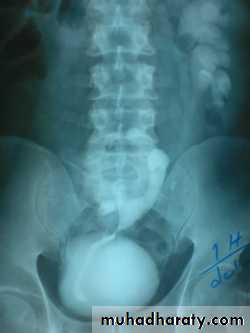

Infantile hydronephrosis ( PUJ OBSTRUCTION ):

IVU shows :

Marked dilatation of pelvis and may be extra-renal.

Calyceal dilatation is late and in advanced cases form foot shape PCS

The ureter is not seen and when it is seen looksnormal .

Delayed film with I.V. diuretic produce gross dilatation .